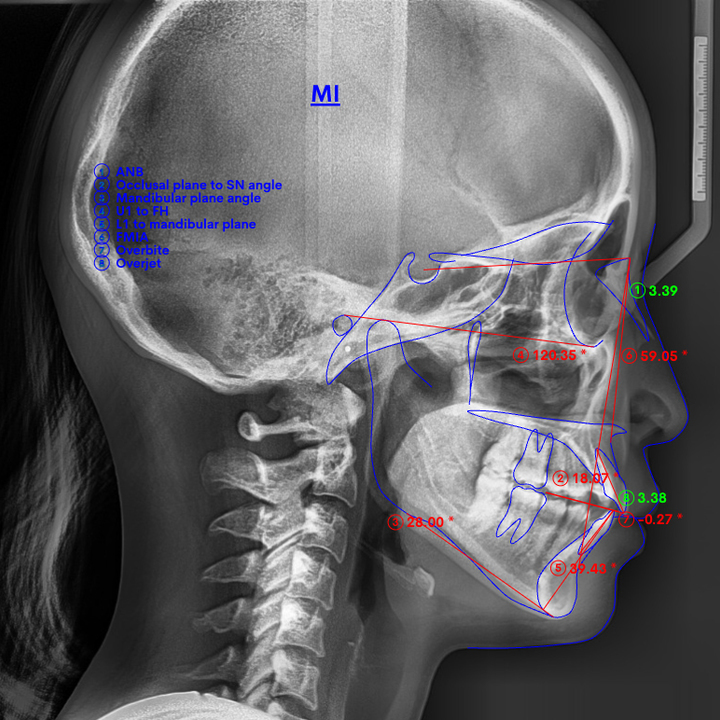

精密検査

(パノラマ・セファロ)